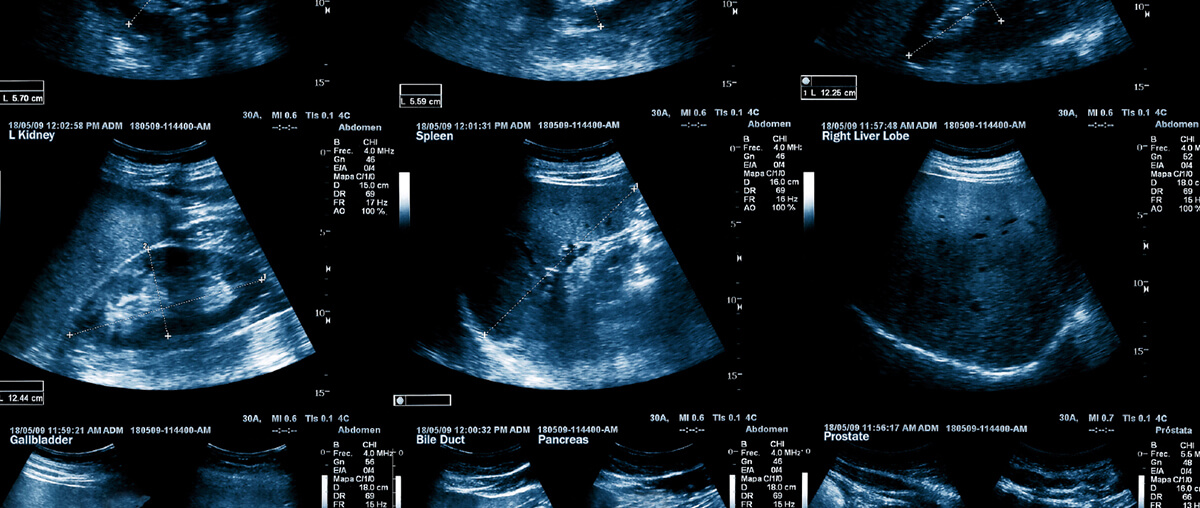

State of the Art Equipment and Friendly Sonographers

Our ultrasound solution provides everything to perform ultrasound exams in your office.